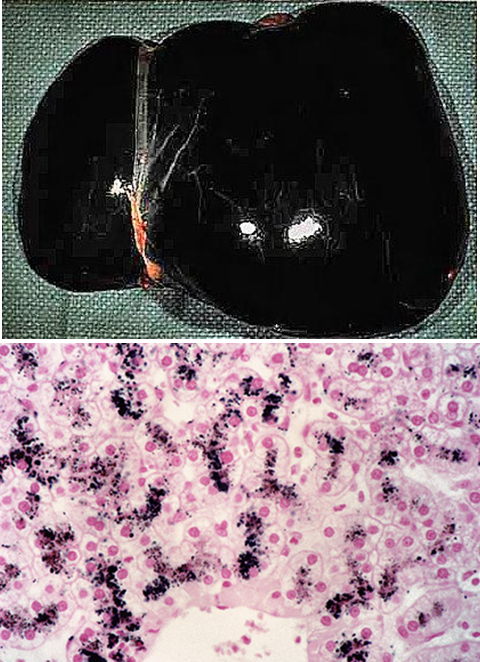

rare autosomal recessive disease ABCC2 (MRP2) gene mutation

defect in bilirubin canalicular transport protein, decreased bilirubin excretion → buildup of conjugated bilirubin, leaks into blood → dark pigment , liver appears black,

ASx and not clinical significant

coproporphyrin excretion is normal

dubin johnson syndrome

dark pigment in dubin johnson accumulates in ______ and contains ______

hepatocye lysosomes

epinephrine metabolites